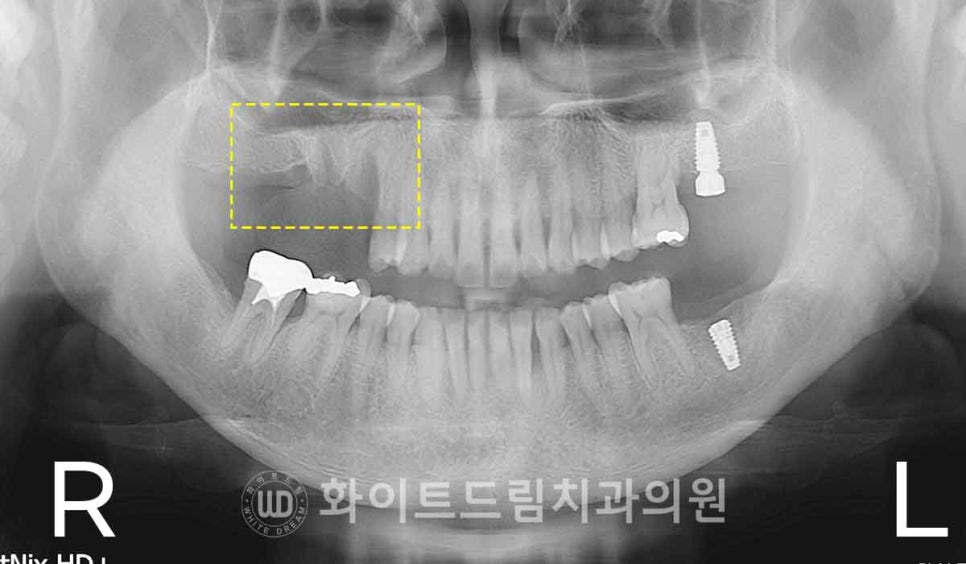

▲ 오른쪽 상악 어금니 발치, 왼쪽 수술 한 달 뒤 발치 : 17.01.13 / 강남역치과 임플란트

환자분의 경우 왼쪽 상악은 1월에 발치를 먼저 진행하고,

약 두 달 동안 잇몸뼈가 회복될 시간을 준 뒤

3월에 임플란트를 식립하는 방식으로 치료를 진행하게 되었습니다.

발치 후 2개월의 회복 기간은

염증이 정리되고 연조직이 아물며,

뼈 표면이 안정화되는 중요한 치유 기간입니다.

특히 왼쪽 상악처럼

골흡수가 심하거나 상악동과의 거리가 너무 가까운 부위는

발치 당일 바로 임플란트를 심으면

초기 고정이 잘 나오지 않아 실패 위험이 높기 때문에

발치 후 일정 기간 치유를 거친 뒤

안정된 골 환경 위에 임플란트를 심는 것이

가장 좋은 예후를 기대할 수 있는 치료 방식이랍니다. ^^